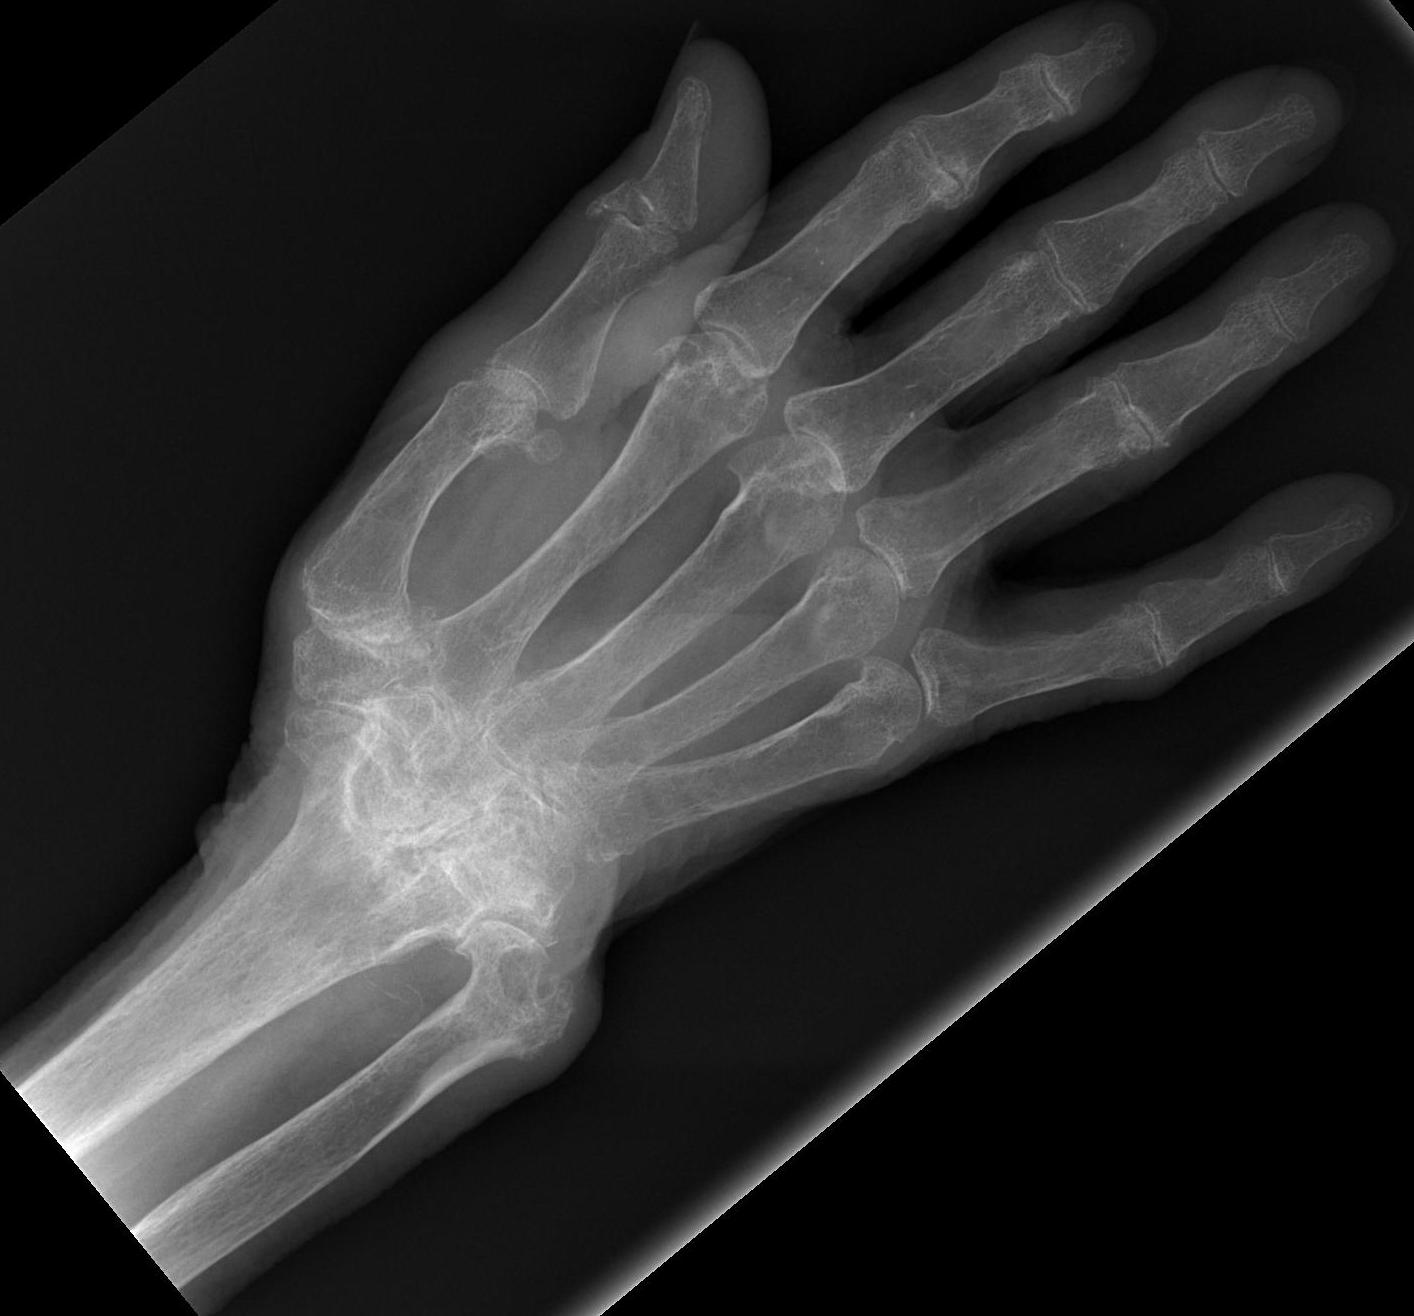

Ulna drift & volar dislocation

Ulna Drift / Ulna Dislocation

Extremely common

- 90% by 10 years have wrist problems

Landsmeer 1961

- treat wrist at same time as treat fingers or will recur